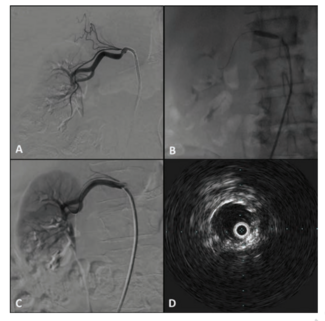

The authors report the first use of the CorPath GRX Robotic System for assistance during balloon angioplasty and stenting for the treatment of severe bilateral renal artery stenosis.